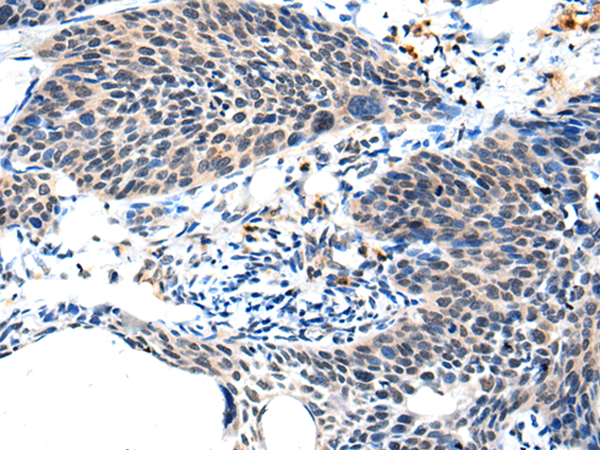

IHC positive control: |

Human cervical cancer and human tonsil |

IHC Recommend dilution: |

25-100 |